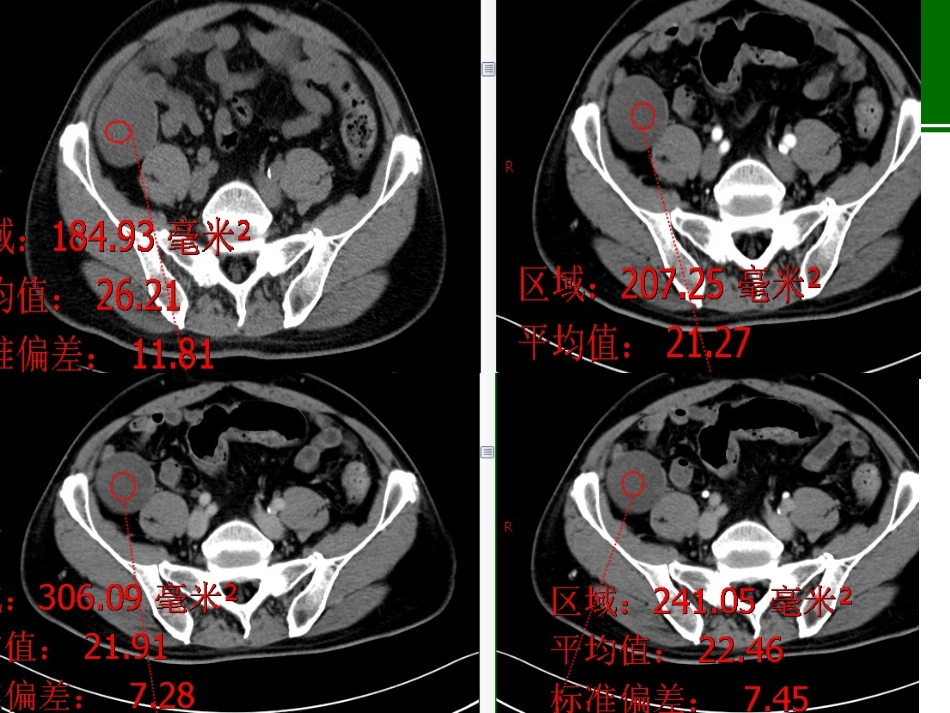

病例•男性,74岁,右下腹痛一月余,无腰背部痛及放射痛,无畏寒及发热。无肿瘤病史。•血象未见明显异常。阑尾粘液性肿瘤阑尾粘液性肿瘤:影像学表现阑尾粘液性肿瘤的典型影像学表现为:粘液囊肿。良性:阑尾黏液性囊腺瘤,粘膜层轻度异性增生、不向腔内突出、不累及肌层及浆膜层是其影像上囊壁厚薄均匀、光滑完整和均匀强化的病理基础。CT:平扫多表现为回盲部球形或类圆形囊性占位,长径小于6cm,长短径比值1.0~2.05,平均1.65;囊壁均匀菲薄,内壁较光整,囊壁可见弧形钙化,囊液密度较均匀,境界清,无分隔,少数病例周围可有少许渗出。CT增强后囊壁均匀强化,囊液无明显强化。影像学表现阑尾低级别粘液性肿瘤:位置:回盲部、右髂窝囊性占位。形态:长茄子形、不规则形、椭圆形或球形,破裂形成腹腔假黏液瘤,囊壁及钙化漂浮在黏液中。大小:长径/短径比值1.2~3.5,平均2.1。囊壁:可较均匀也可厚薄不均,多毛糙。根蒂:不均匀增厚,可见壁结节;盲肠内可见黏液。钙化:附壁蛋壳样钙化或囊内颗粒样钙化。囊内容物:密度较高,可见絮状强化。强化:囊壁轻中度强化;可出现环形强化及囊内絮状、分隔样强化。假性粘液瘤:少见。影像学表现阑尾粘液腺癌:易穿破浆膜形成腹膜假性黏液瘤及腹腔种植,少数可直接穿孔形成窦道,经窦道侵犯其他脏器;病灶粘膜向腔内突出,并可见游离实质性成分及漂浮异型细胞,并向肌层及浆膜层浸润生长是影像上囊壁厚薄不均匀,毛糙不光滑,囊液不均匀和增强后不均匀强化和条絮样强化的病理基础。肿块内实性成分更多,增强后明显强化。常伴有腹膜假性粘液瘤。鉴别诊断阑尾炎性病变:单纯阑尾炎,阑尾增粗形态存在,黏液较少,密度较低,根部可有粪石,但囊内及囊壁不会有钙化。脓肿临床表现为高热、白细胞明显增高等症状;阑尾壁水肿增厚明显,无壁结节,增强后明显环形强化,周围渗出明显。结核等炎性病变可以伴腹水,腹水密度较低,无分隔条絮样强化,无腹腔种植转移,结核冷脓肿多无钙化,与阑尾不相连。结核慢性期钙化明显,伴有淋巴结钙化、肿大及干酪样坏死;阑尾黏液性肿瘤不累及淋巴结,发现淋巴结异常支持结核或其他肿瘤。鉴别诊断阑尾黏液囊肿是指阑尾出口梗阻,导致阑尾腔扩张并黏液聚集所形成的囊性占位病变,一般阑尾根部可见粪石嵌顿而非肿瘤性软组织,病变较小,一般直径<2cm,囊壁均匀较薄光滑,一般不超过3mm,内无分隔,无壁结节,特殊染色PAS(一)。阑尾其他肿瘤多以实性为主,发生坏死囊变时,可表现为囊实性,但肿瘤实性成分比例高,且囊壁厚,囊内壁更不光整,周围可有肿大淋巴结。阑尾黏液性肿瘤主要为囊性,实性成分少,主要位于根蒂或囊壁。鉴别诊断系膜囊肿或前肠囊肿:为圆形或椭圆形等囊性包块,无明显根蒂,与系膜或肠管关系可较密切,囊壁均匀光整,囊液密度较低,结合钙化位置形态及增强后强化特点不难鉴别。(正常阑尾结构)右侧附件来源肿瘤:部分病灶定位困难总结•阑尾黏液性肿瘤分为良性的囊腺瘤、低度恶性的低级别黏液性肿瘤、恶性的黏液腺癌;黏液性肿瘤有一个从粘膜增生到瘤变再过渡为LAMN,最后癌变的逐步演变过程;•影像观察病灶部位、大小、形态、境界、根蒂和囊壁(厚度、均匀度、光滑度、完整度)、内容物(壁结节、分隔、钙化、囊液、气体)、强化(强度、均匀性、方式)、腹水、假性粘液瘤。•粘液性囊腺瘤一般局限在阑尾内,腹腔无粘液成分,囊液清、均匀,壁薄;•低级别黏液性肿瘤恶性度较低,影像表现介于黏液腺癌与囊腺瘤之间。•参考文献: